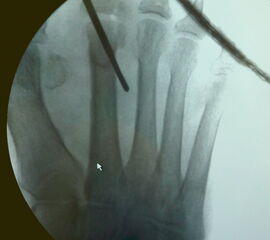

• Unter Durchleuchtungskontrolle Positionieren der Shannon-Fräse mit 20 mm langem und 2 mm dicken Fräsenkopf in 45° Neigung an den Hals des Metatarsale (siehe Abbildung 3 a und b).

• Verschieben der Fräsenspitze um wenige Millimeter nach proximal.

• Röntgenkontrolle, um die korrekte Position von Fräsenspitze bzw. Osteotomieebene an der distalen Diaphyse des Metatarsale-Knochens zu bestätigen (Abbildung 3 c).

• Beginn der Osteotomie im Winkel von 45° zur Längsachse des Os metatarsale in einer von dorsal-distal nach proximal-plantar-reichenden Ebene.

Zum Lesen der Bildbeschreibung und zur Vollansicht bitte die Bilder anklicken. Bilder: A. Mehlhorn.